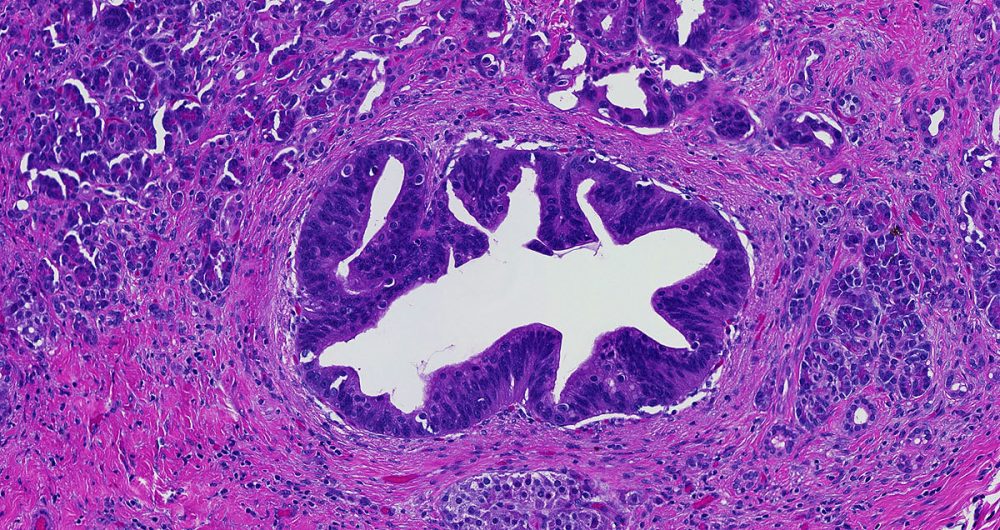

High-grade pancreatic intraepithelial neoplasia replaces the older term- PanIN-3.